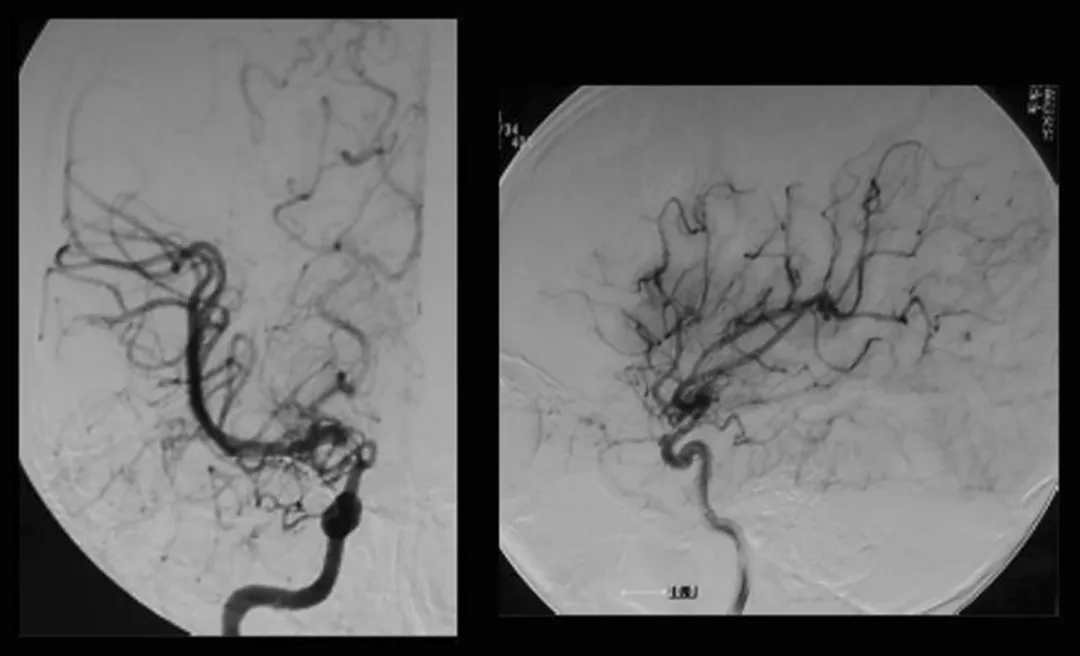

烟雾病是一种特殊的脑血管疾病双侧颈内动脉慢慢变窄,大脑底部长出密密麻麻的烟雾状代偿血管网。 对于成年患者,直接搭桥手术是目前最有效的治疗方式之一:把头皮上的颞浅动脉接到大...

在神经外科领域,烟雾病一直是个棘手难题。患者大脑主要血管逐渐闭塞,代偿形成脆弱异常的烟雾状血管网,不仅容易导致脑缺血,更可能在搭桥手术后出现致命的出血性脑高灌注综合征(...

烟雾病患者接受颞浅动脉-大脑中动脉(STA-MCA)双吻合术,就像为缺血的大脑搭建生命通道,但术后潜藏的出血性脑高灌注综合征(CHS),却可能成为致命隐患。 INC国际神经外科脑血管大咖川岛...